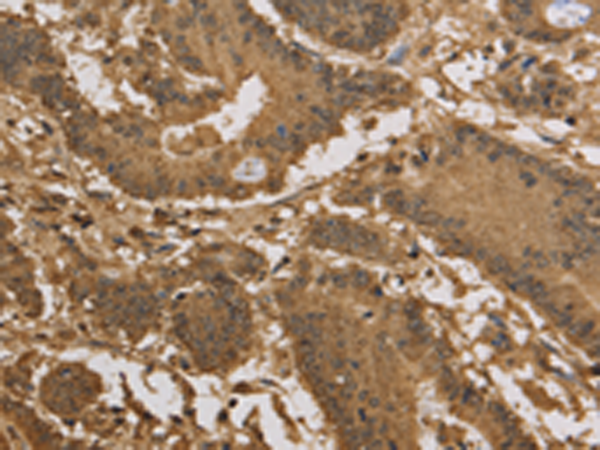

分类: 科研抗体货号: P05127别名: P2X2; DFNA41应用: WB,IHC反应种属: Human, Mouse